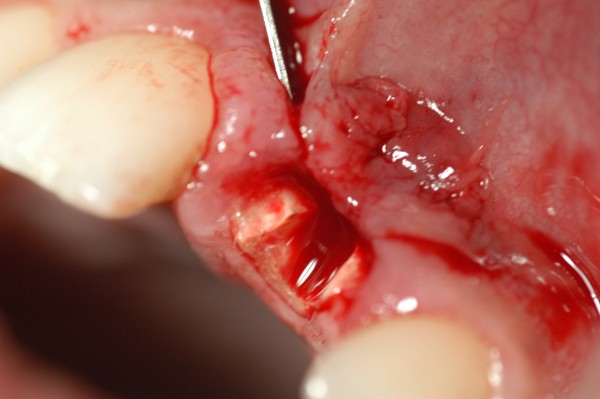

Observado por vestibular, el diente presentaba un botón fistuloso que no había sido advertido por el paciente.

Fig.02(Pie de foto: Fístula)

Fig 09(Pie de foto: Exodoncia porción coronal)

Fig.10(Pie de foto: remanente cortical)

Fig.11 Fig.12(Pie de foto: Incisión)

A.I.D.A.(Avulsionador Intradentario Atraumático.)

Fig.15 Fig.16(Pie de foto: A.I.D.A.)

Fig.17(Pie de foto: Preservación de la cresta remanente)